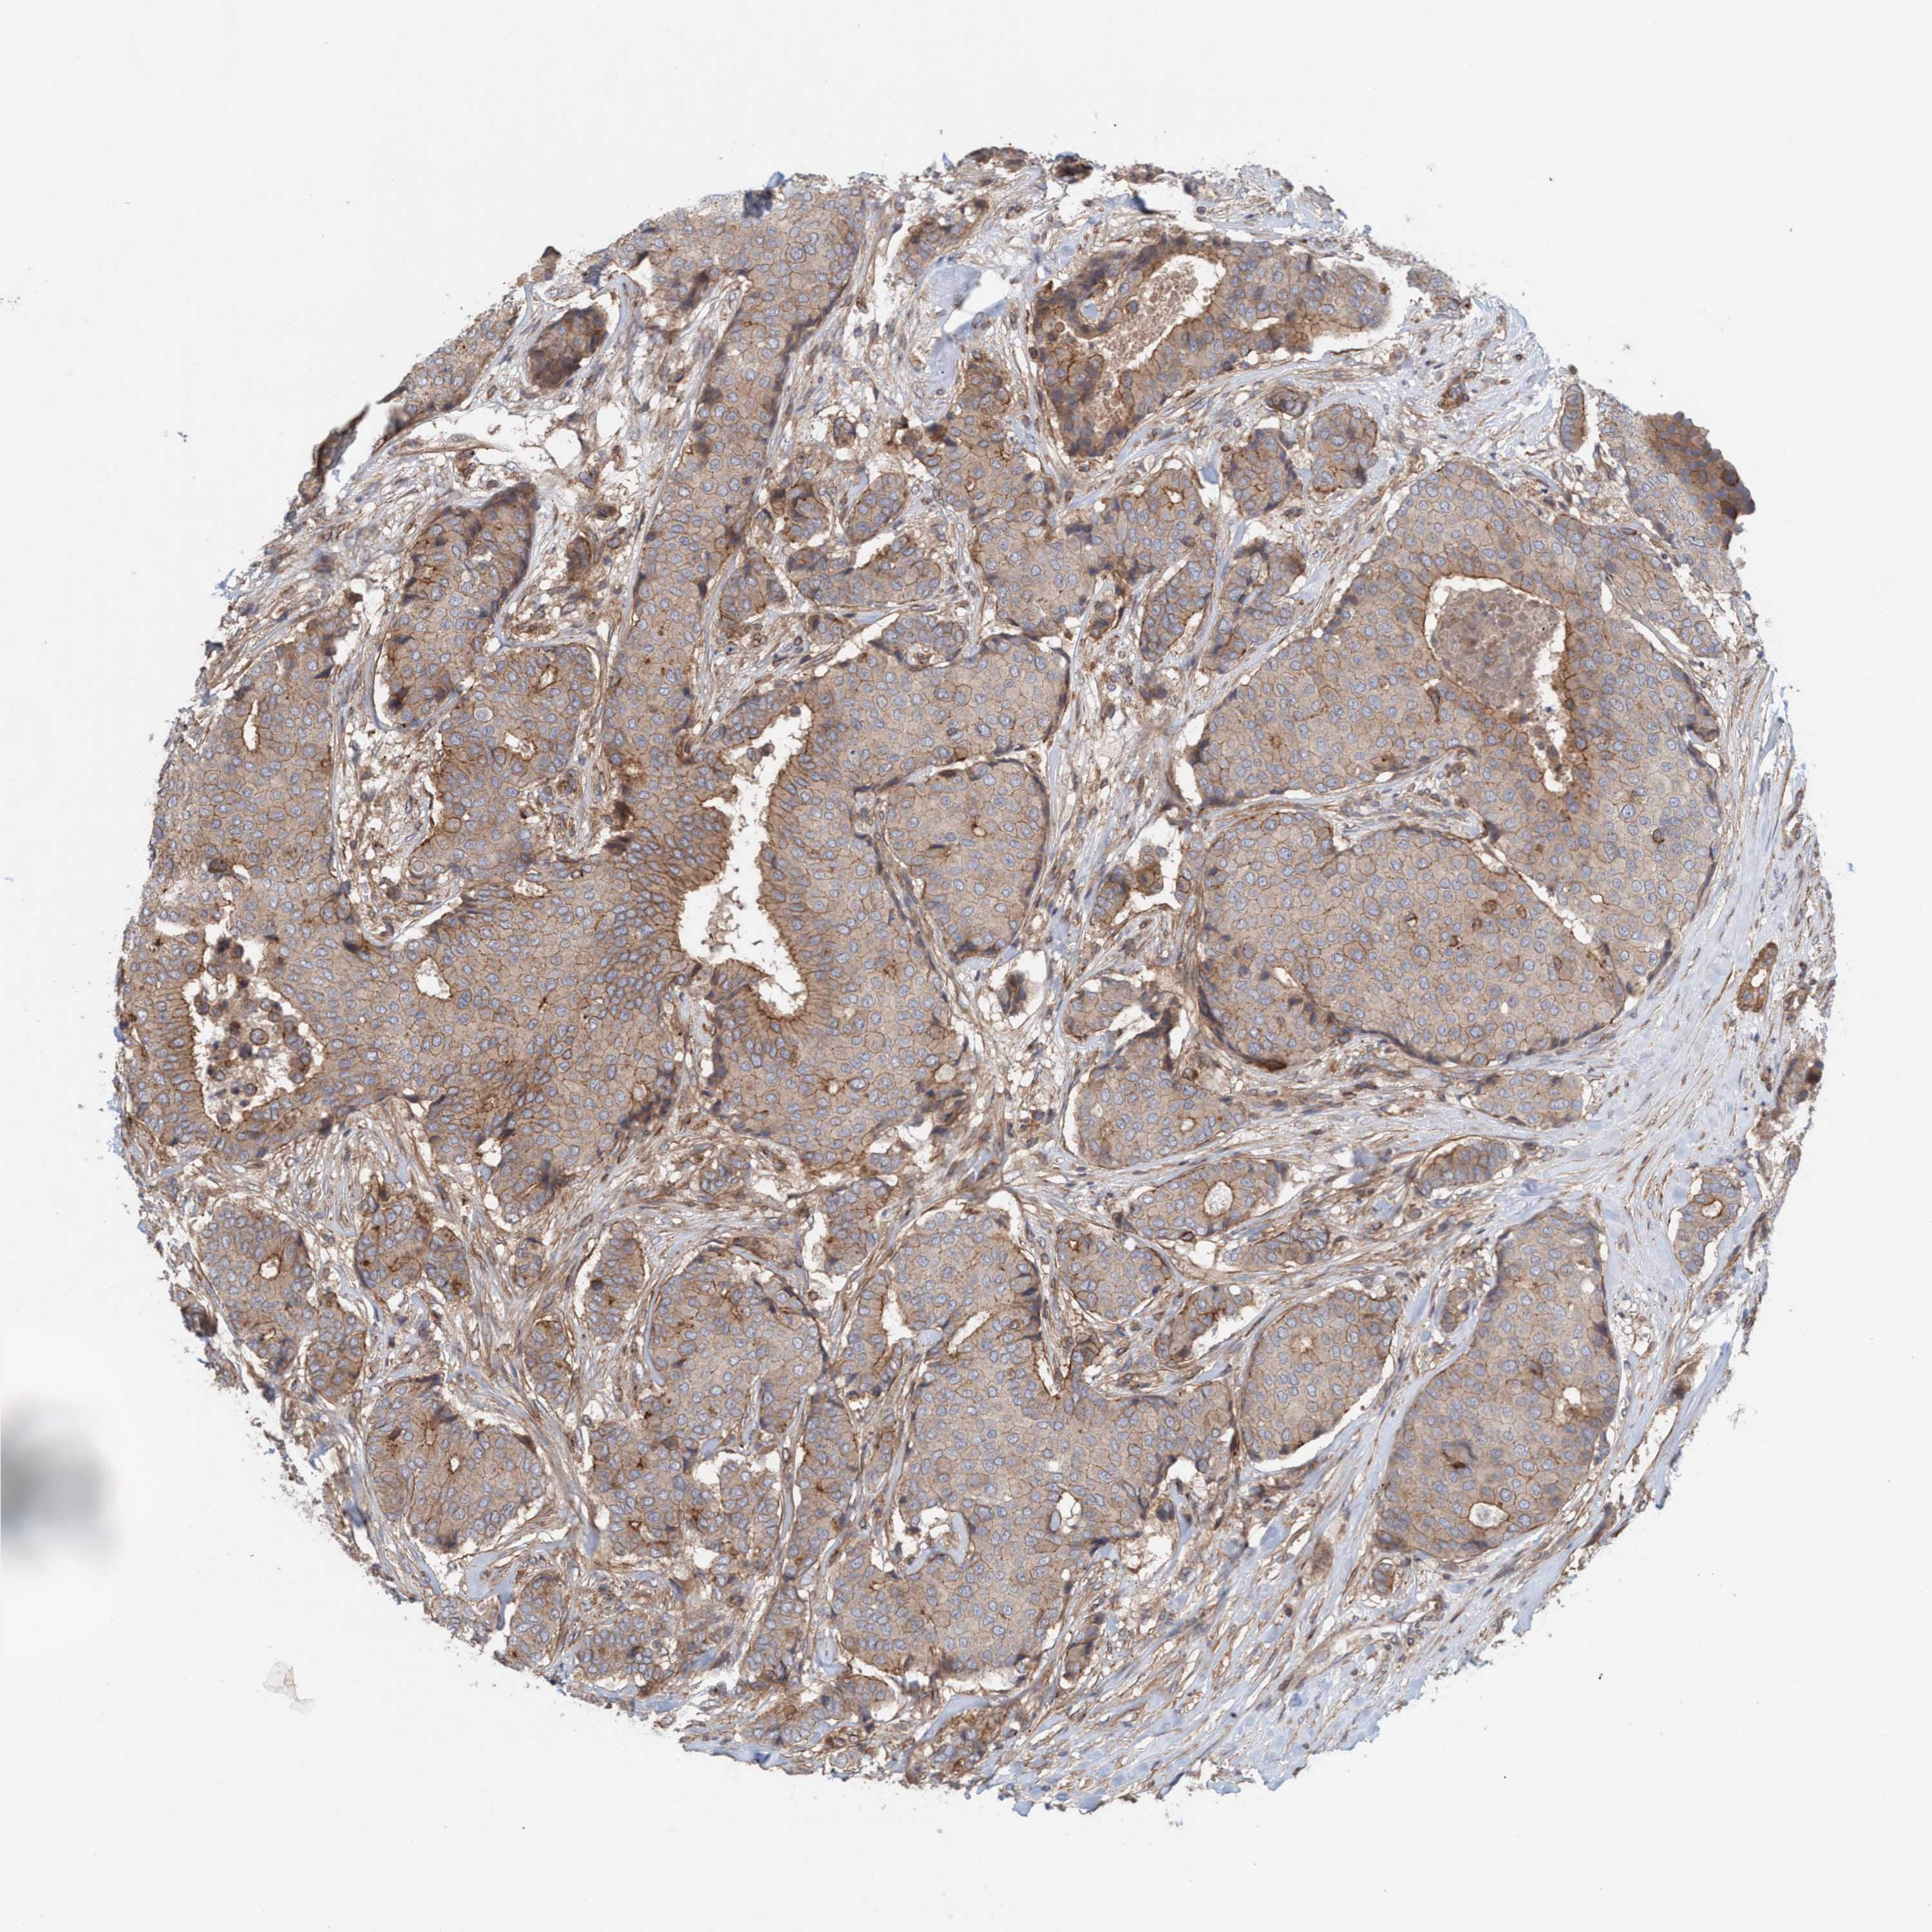

CANCER BREAST CANCER Show tissue menu

BRCA TCGA BRCA VALIDATION PROTEIN EXPRESSION